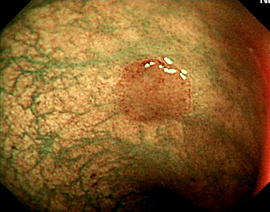

2002年、世界ではじめて「ハイビジョン内視鏡システム」が生まれ、内視鏡検査の技術が大きく革新しました。ハイビジョンとLCDモニターが今まで以上に高画質、高品質な画像で検査が可能となったのです。

内視鏡の欠点は微細な凹凸がわからないところでしたが、粘膜のわずかな変化を強調表示する「IHb色彩強調機能」が搭載され、わかりにくい病変がはっきり観察できるようになったのです。

色をつけることにより凸凹がはっきりします。

また、動画や静止画像の電子的拡大が可能となったため病変の見逃しが激減しています。なにより経鼻内視鏡(鼻から入れる内視鏡)の誕生や径が細くなったことなどで、挿入時の負担が減りました。病院によっては軽い麻酔薬を使っての検査も可能です。